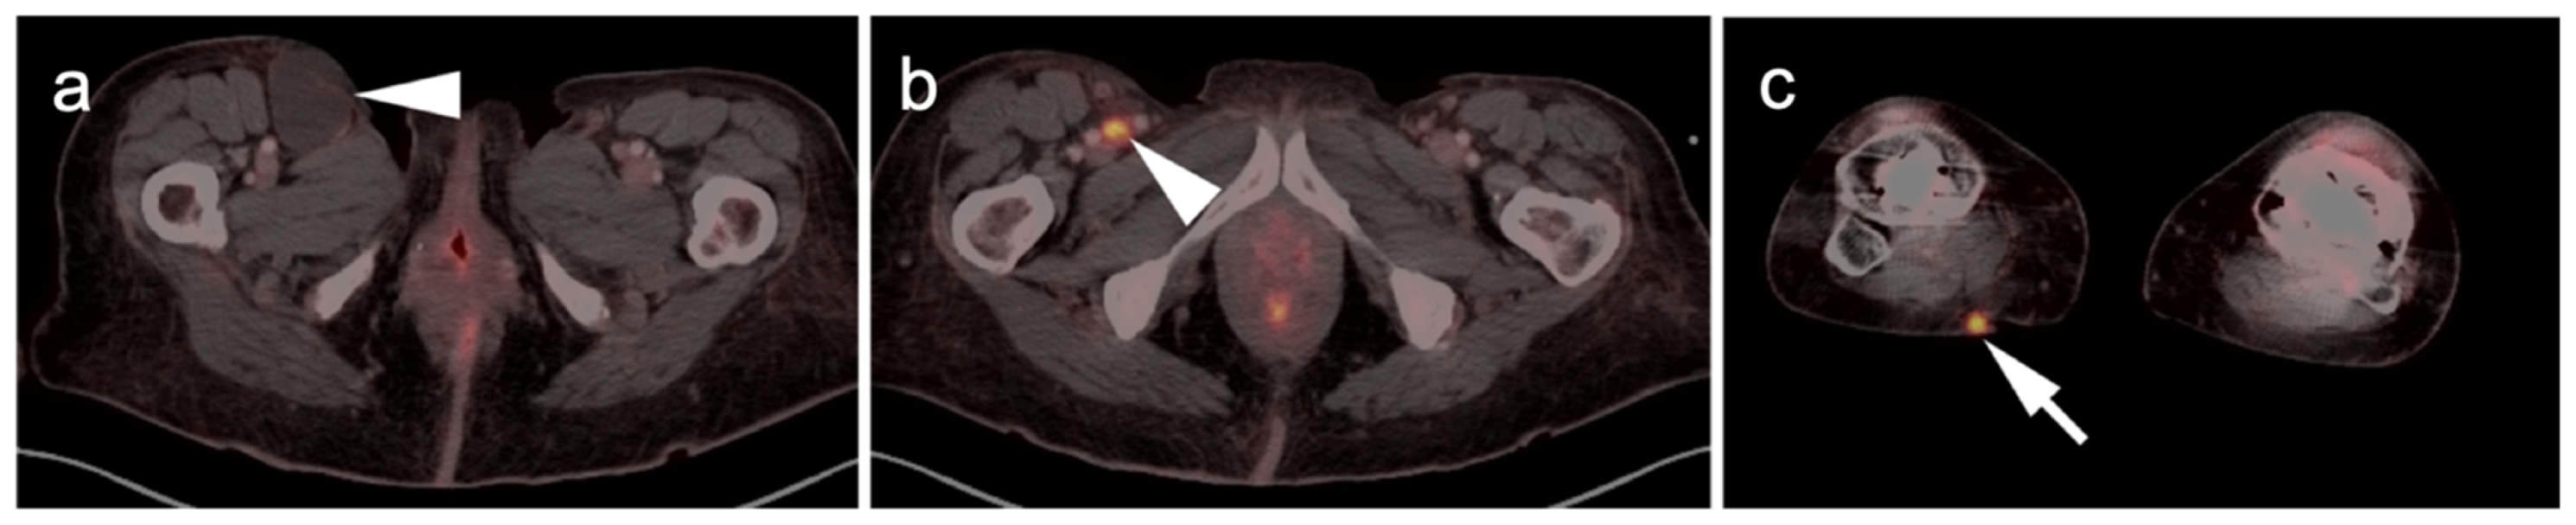

3.1.5. Rhabdomyosarcoma

3.1.8. Nerve Sheath Tumors